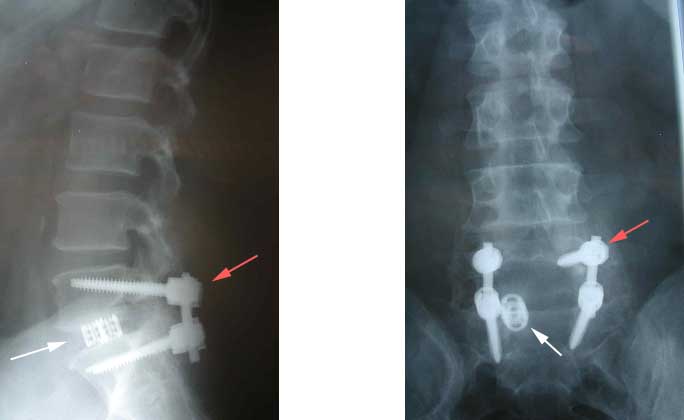

Fusions can also be performed from the back where screws can be placed. The figure below shows screws [marked by red arrows] and a cage [marked by white arrow] placed into the spine by going through the back side of the patient.